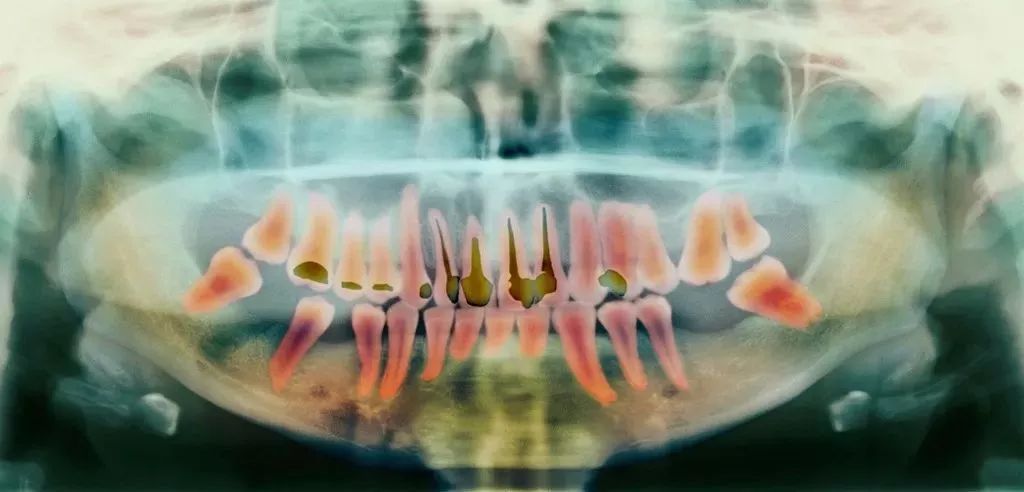

这是目前最有效、最常见的治疗牙髓病和根尖周病的方式,可以消除牙齿内部炎症及其病变源,预防炎症加重扩散,从根本治愈。

一般来说,当你的牙齿遇到下面这些情况:

- 蛀牙坏到牙齿内部,牙髓或细菌感染引起了急/慢性牙髓炎;

- 牙髓由于长期刺激或其它原因造成的死髓牙;

- 意外磕碰、外伤,导致牙根尖血管断裂引起牙神经暴露;

其过程就是先将牙齿内部坏死的牙髓清理干净,再放入永久性消炎杀菌的药物,最后进行冠修复来拯救这颗牙齿。